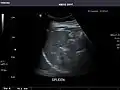

Spleen